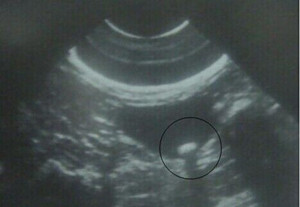

一、B超检查:该项检查具有方便、诊断准确性高的优点。特别是针对胆囊结石,诊断准确率可达95%以上。

四、腹部超音波检查:超音波对胆结石来说是相当理想的一种检查,是目前常用而且又无痛的方法,也不会使人暴露在放射线下,即使是怀孕中的妇女或是婴幼儿均可完全放心。它的诊断准确度可达90%-95%;需要注意的是,检查的前一天晚上十点到第二天检查结束之前,不能吃任何东西,需要空腹。>>>胆结石做检查前要注意什么呢?

温馨提示:B超检查能明确结石的大小、多少,而其它检查是需要进一步明确胆囊功能如何,这样专家才能根据你的情况,为你制定专业的治疗方法。